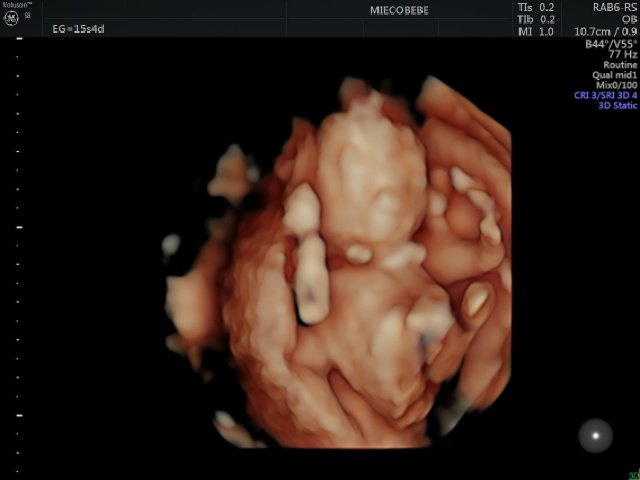

#infertilpreñis #infertilmamis Ayer la eco fue muy bien, aunque bebé se quiso esconder en la placenta a mitad de la eco y de ahí no se movió 🤭 Hicimos revelación en la misma clínica con 🎈 y es... ¡NIÑA! 🦔💜

#infertilpreñis LARA. Tenías que ser tú. Gracias por quedarte y elegirnos como padres. 2025 va a ser el año más bonito de nuestras vidas porque tú llegarás 💜